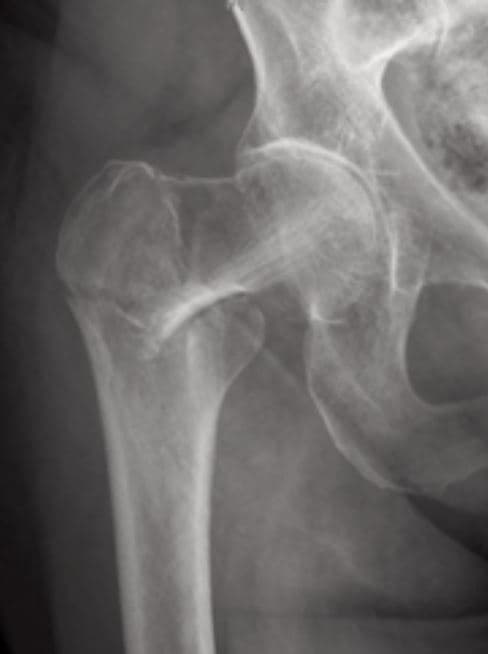

Describe the fracture

Determine an approximate age range for this female patient. Explain why you chose that age.

Is this pelvis male or female? Explain